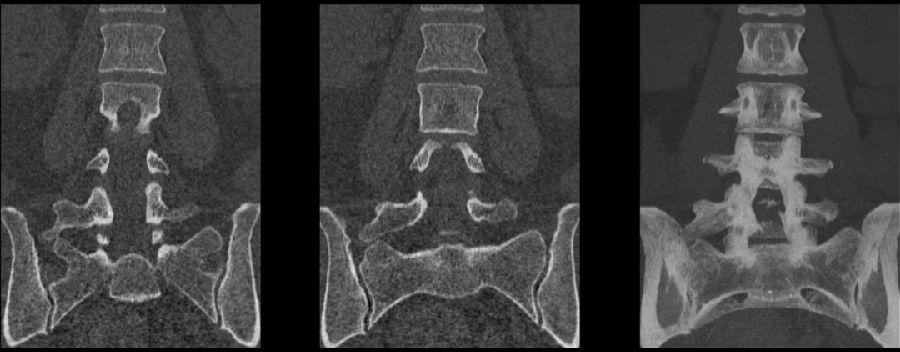

目前,腰骶移行椎以Castellvi的分类方法最为常用。其主要根据横突形态及其与骶骨、髂骨是否融合或形成假关节而分为4型,Ⅰ、Ⅱ、Ⅲ型又根据单、双侧分为A、B两个亚型。

I型:主要为腰5横突发育不良,横突宽度大于19mm,并将其分为两个亚型Ia(单侧横突发育不良)或Ib(双侧横突发育不良)

L5右侧横突肥大,为Ⅰa型

L5双侧横突肥大,为Ⅰb型

II型:表现为不完全的腰椎骶化,具有增宽的横突,并且和骶骨形成假关节,并将其分为两个亚型IIa(单侧关节形成)或IIb(双侧关节形成)

L5左侧横突肥大,假关节形成,为Ⅱa型

L5双侧横突肥大,假关节形成,为Ⅱb型

III型:单侧(IIIa)或双侧(IIIb)腰椎完全骶化,腰5横突与骶骨完全骨性融合

L5右侧横突肥大与骶骨发生骨性融合,为Ⅲa型

L5双侧横突与骶骨骨性融合,为Ⅲb型

IV型:一侧为II型即腰5横突与骶骨形成假关节,对侧为III型即腰5横突与骶骨形成骨性融合

IV型即混合型:L5双侧横突肥大,一侧与骶骨相接触为Ⅱ型表现,另一侧与骶骨形成骨性融合为Ⅲ型